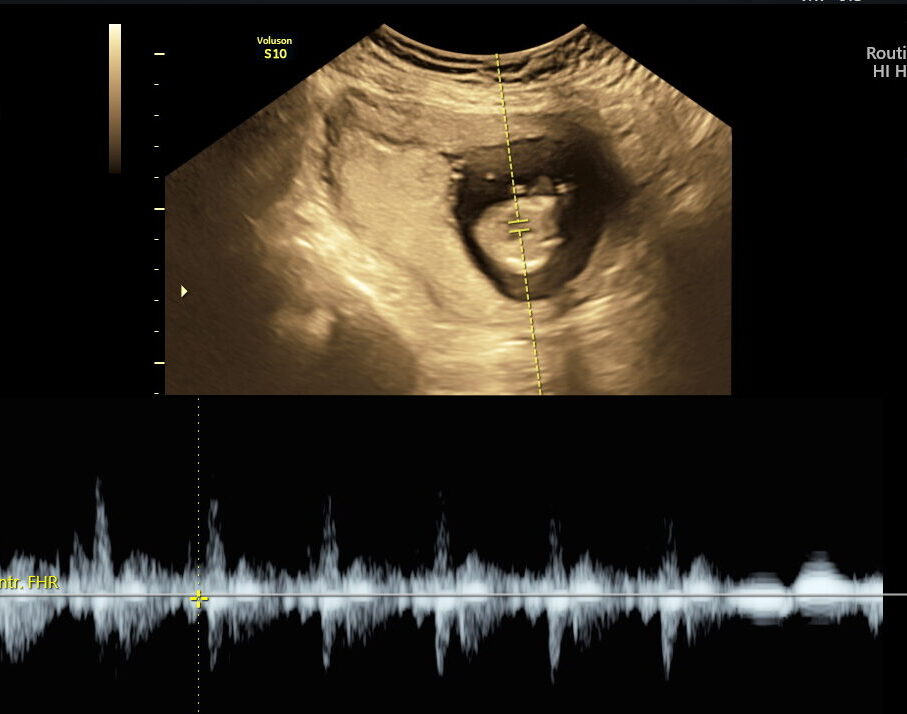

CVS is an early genetic test done between 10–13 weeks of pregnancy. A tiny sample of placental tissue (chorionic villi) is taken to analyze the baby’s chromosomes. CVS provides early answers for families at risk of genetic disorders or who have had abnormal screening results. Unlike screening tests that estimate risk, CVS provides clear, laboratory-confirmed answers. It is performed in the first trimester, making it one of the earliest opportunities for definitive genetic diagnosis during pregnancy.

CVS is typically performed between 10–13 weeks of pregnancy.

- High-resolution ultrasound guidance ensures accurate sampling and minimal risk